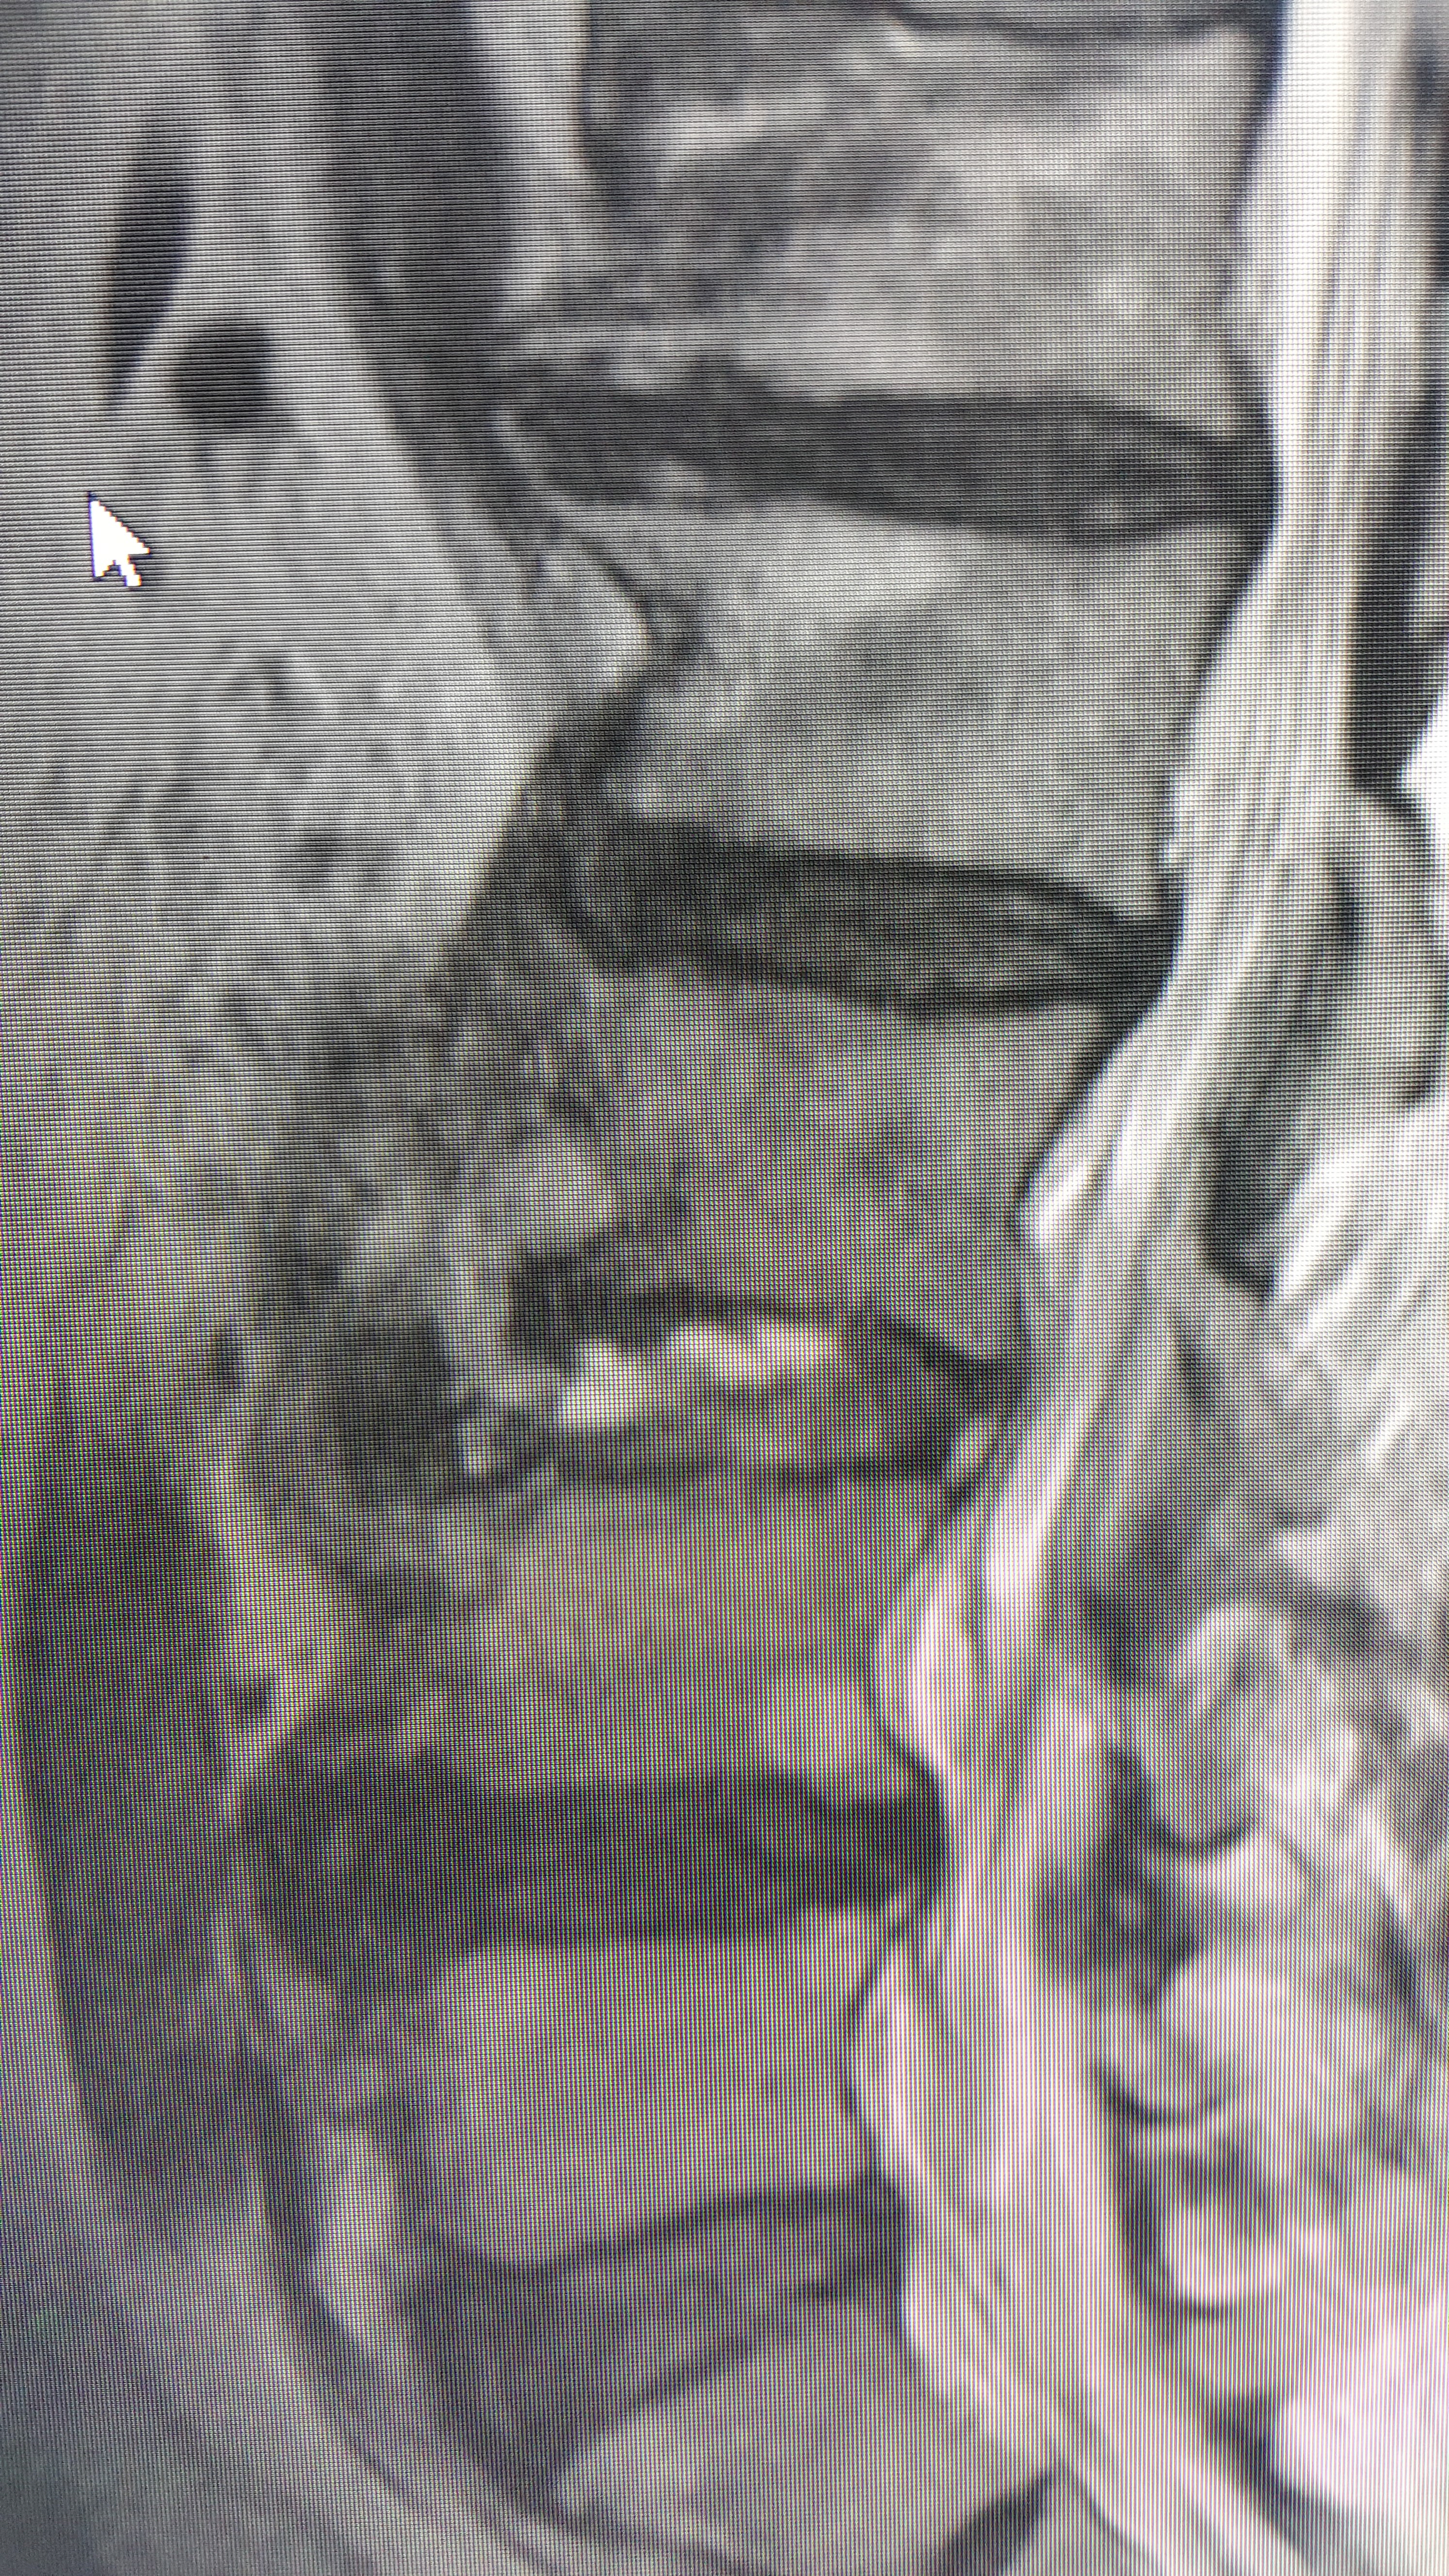

»çÁøCT/MRI